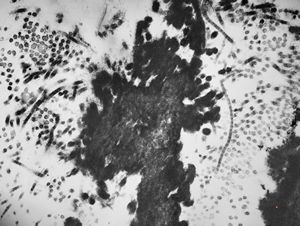

F,49y. | purulent meningitis- meningococcal v.s.

F,49y. | purulent meningitis- meningococcal v.s.

F,49y. | purulent meningitis- meningococcal v.s.